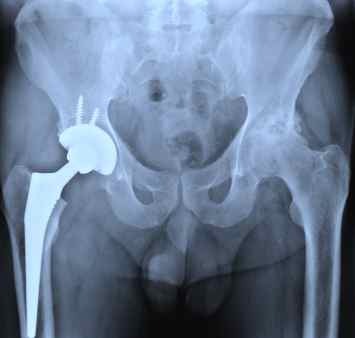

Hip replacement This is how both hip replacements look on an x-ray Statistically, a fracture occurs in 90% of cases at the age of 60+ and in women. The reason here is osteoporosis (leaching of calcium from bones) during menopause . . . . #HipReplacement #Orthopedics #Xray

Smart1Doctor1's tweet image. Hip replacement

This is how both hip replacements look on an x-ray

Statistically, a fracture occurs in 90% of cases at the age of 60+ and in women. The reason here is osteoporosis (leaching of calcium from bones) during menopause